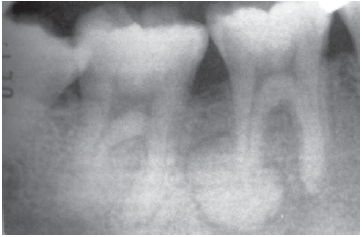

Lesão radiopaca associada à raiz distal do elemento 46.

Paciente do sexo masculino, 25 anos, leucoderma, foi submetido a exame radiográfico periapical completo para iniciar o tratamento ortodôntico. Durante a avaliação de tal exame, o cirurgião-dentista observou uma massa radiopaca apresentando halo radiolúcido no ápice da raiz distal do dente 46 (figura acima). O teste de vitalidade pulpar indicou que esse elemento era vital.